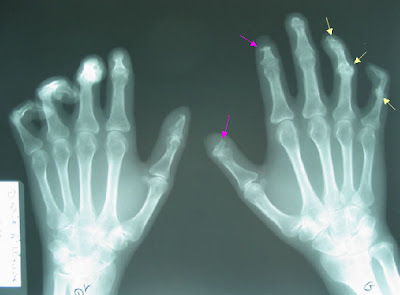

ARTHROPATHY

arthropathy signs and symptoms

arthropathy symptoms